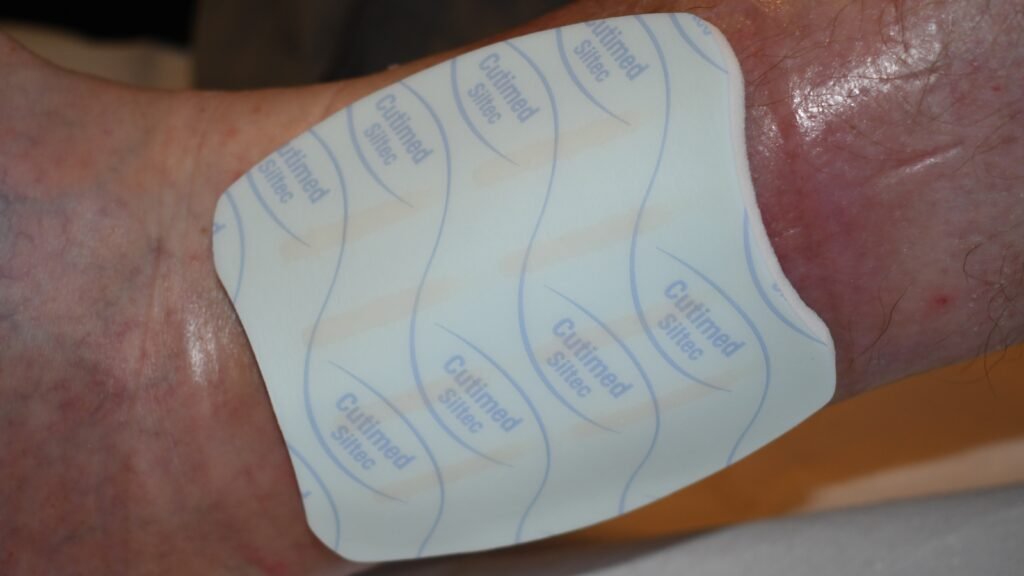

Cutimed Siltec

Silikon-Wundauflagen

Zusätzliche – Fotos ![]() 4 Videos

4 Videos ![]() 1

1